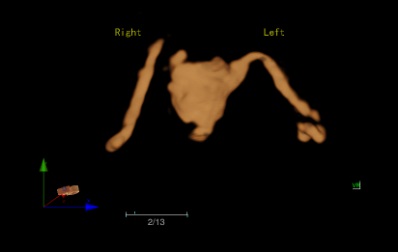

Oviduct 4D Ultrasound Angiography

Oviduct 4D contrast-enhanced ultrasound offers a safer and more effective way for intuitive visualization of oviduct in multiple angles. Great reproductivity in noninvasive operation enables treatment progress monitoring.